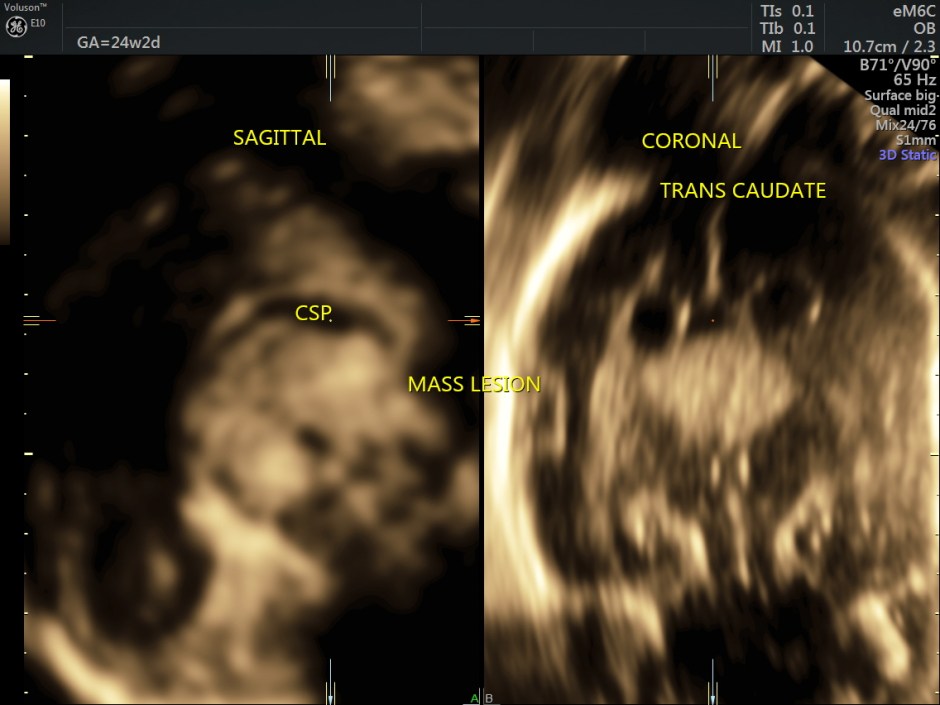

Some reconstructed images are given below.

In this patient, reconstructed images show the corpus callosum to be formed.